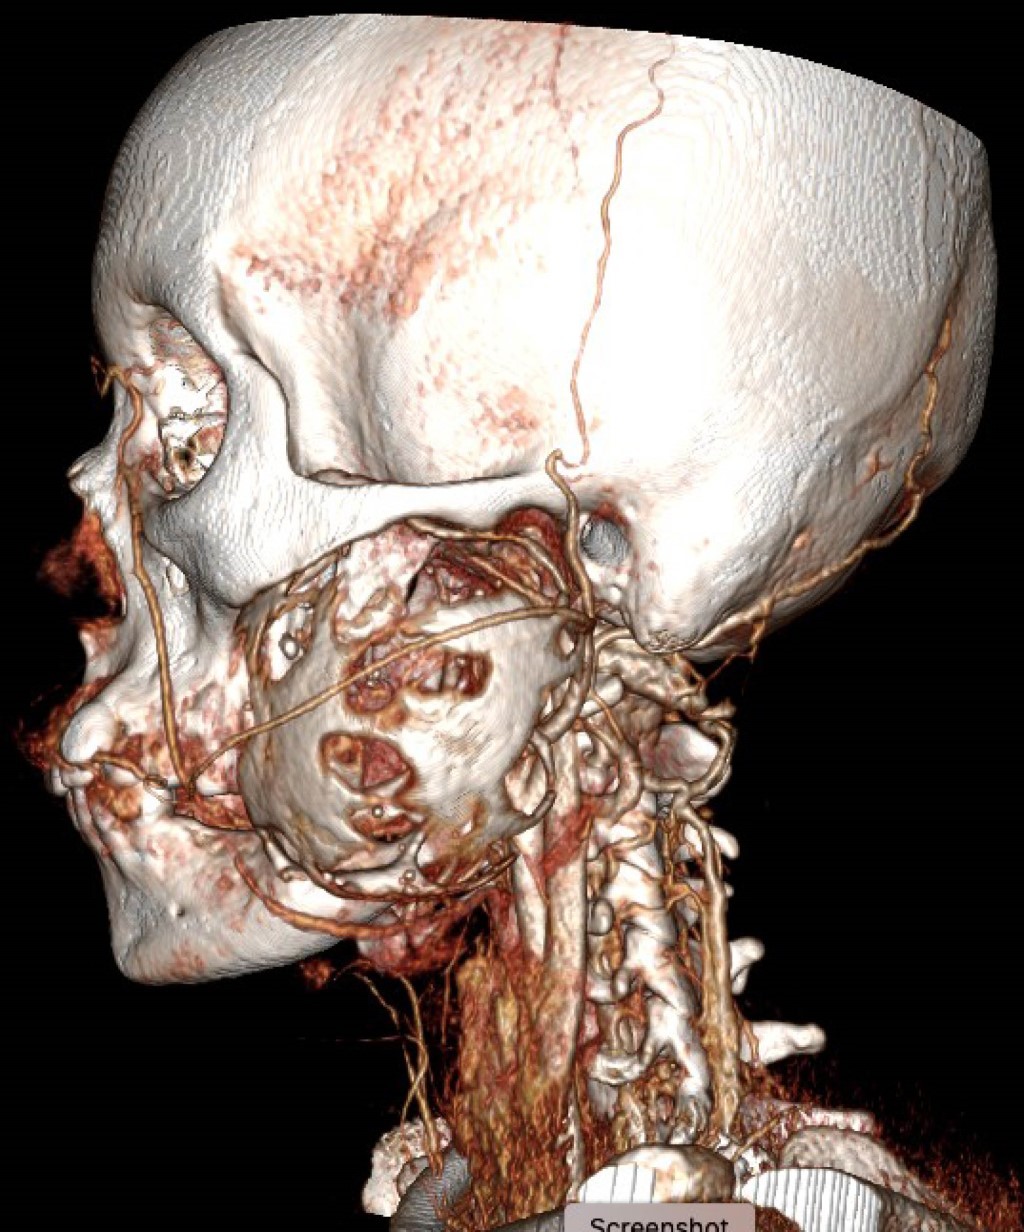

La tomografía contrastada mostró una lesión osteolítica bien delimitada con bordes escleróticos, afectando cóndilo, rama y cuerpo mandibular izquierdo posterior al primer premolar; la lesión medía 56 × 70 × 66 mm, con erosión del maxilar izquierdo y desplazamiento de arteria carótida externa y vena yugular interna (Figuras 2, 3, 4, 5 y 6).

Figura 2

Figura 3

Figura 4

Figura 5

Figura 6